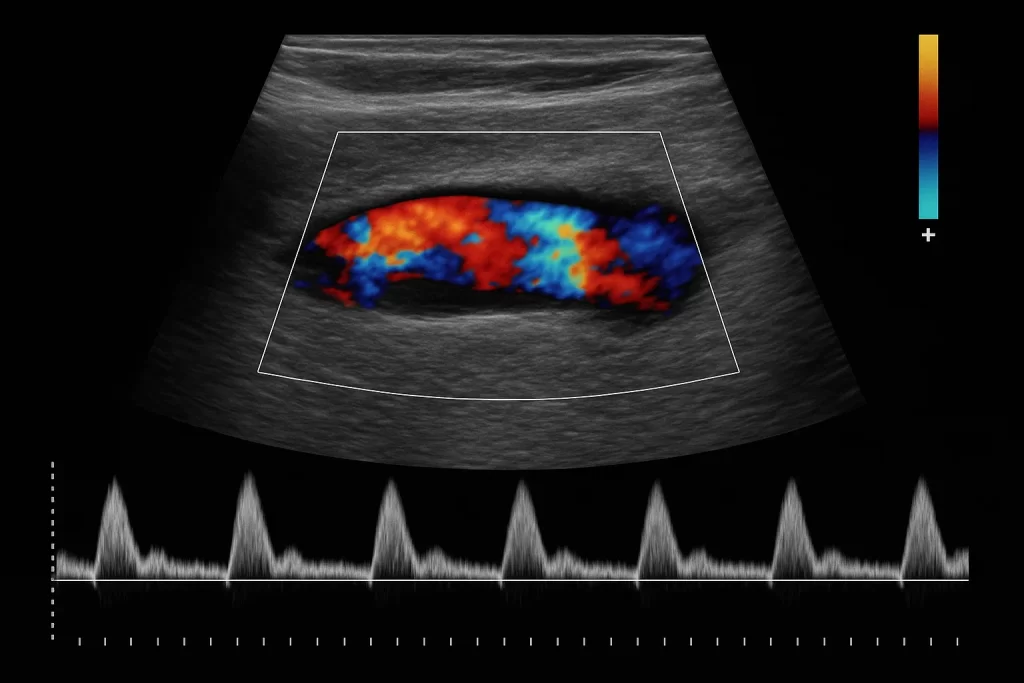

23 مهر دستگاه سونوگرافی سونوگرافی داپلر چیست و چه کاربردهایی در پزشکی مدرن دارد؟ 1404-08-10 توسط zakariakabir_admin 0 نظر در دنیای شگفتانگیز تصویربرداری پزشکی، سونوگرافی استاندارد به مثابه یک پنجره شفاف به داخل بدن انسان عمل میکند. این فناوری به پزشکان اج... ادامه مطلب